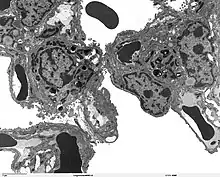

SP-A1 is primarily synthesised in type II alveolar cells in the lung, as part of a complex of lipids and proteins known as pulmonary surfactant. The function of this complex is to reduce surface tension in the alveoli and prevent their collapse during expiration. The protein component of surfactant helps in the modulation of the innate immune response, and inflammatory processes.

The lung is the main site of SFTPA1 synthesis, but SFTPA1 mRNA expression has also been detected in the trachea, prostate, pancreas, thymus, colon, eye, salivary gland and other tissues.[14] Using specific monoclonal antibodies for Surfactant protein A, the protein can be detected in lung alveolar type II pneumocytes, club cells, and alveolar macrophages, but no extrapulmonary SP-A immunoreactivity was observed.[14]